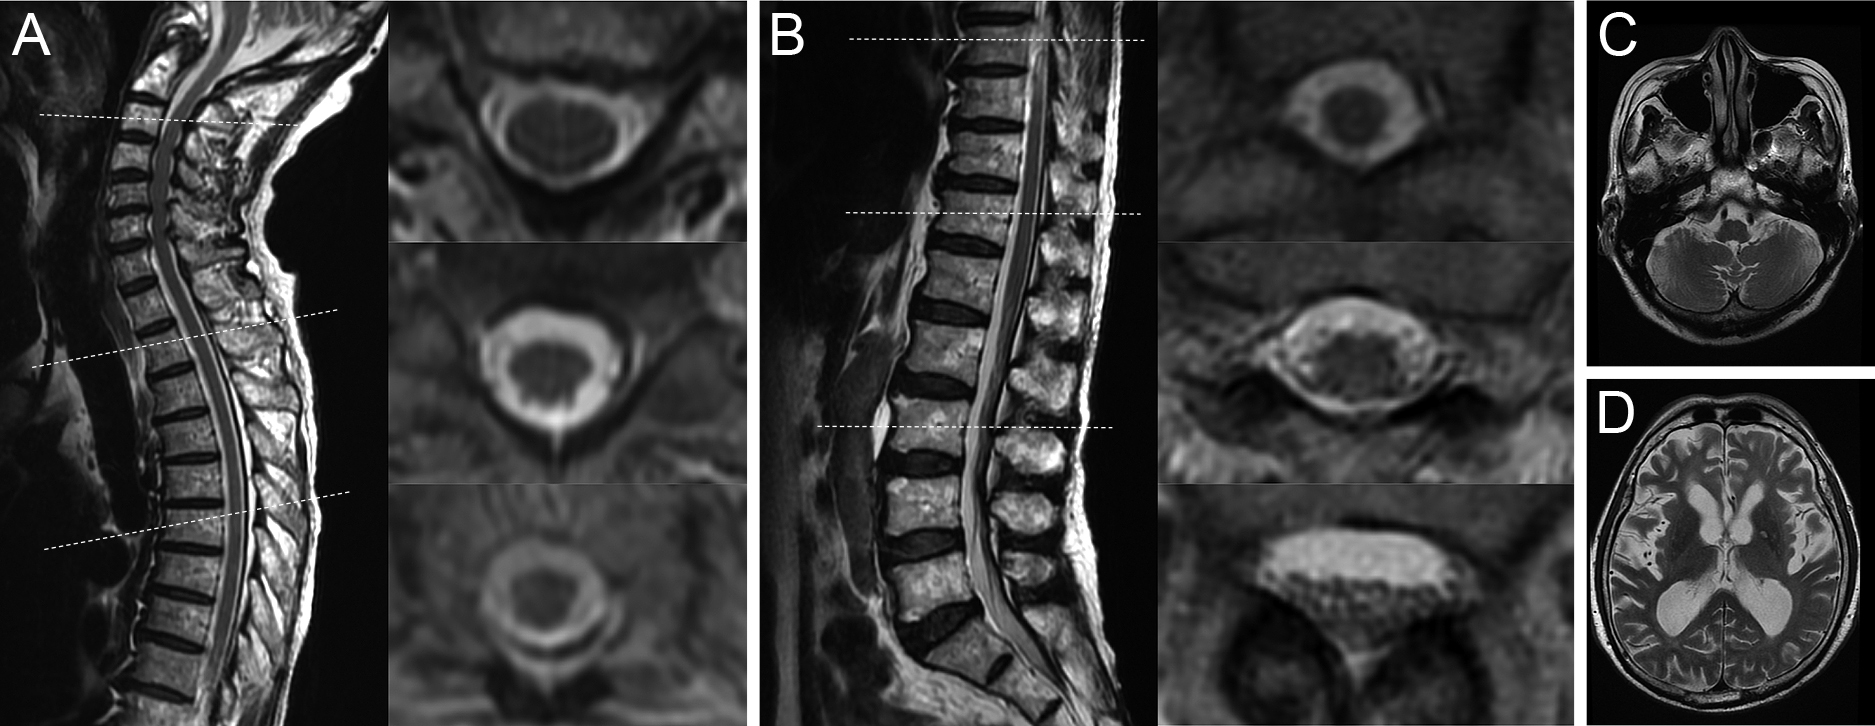

A case of myelin oligodendrocyte glycoprotein antibody-associated disease presenting with radiculopathies

Sunao Takahashi, Takashi Irioka, Ryo Iwase, Susumu Igarashi, Toshiyuki Takahashi

2026/02/13